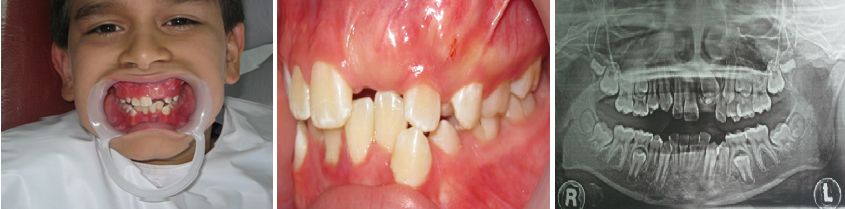

PACIENTE PEDIATRICO DE 10 AÑOS DE EDAD CON DIAGNOSTICO DE ODONTOMA.

PROCEDIMIENTO QUIRURGICO DE ELIMINACION DEL ODONTOMA